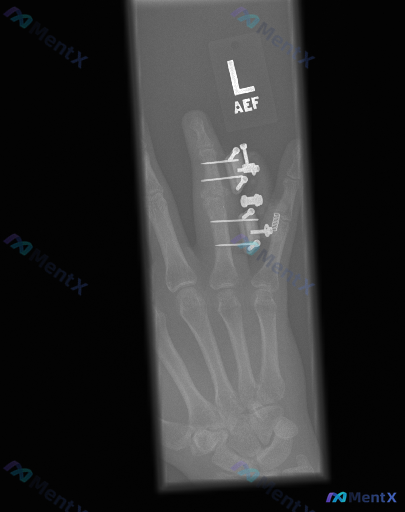

左手无名指内固定术后X光:只看得到手术痕迹,还是藏着其他异常?

整理到一张左手正位X光的读片资料,先看核心信息: - 图像范围:仅显示手掌中、环、小指及部分腕骨 - 明确背景:无名指(环指)近节、中节指骨区可见克氏针、钢板/连接装置及螺旋状金属固定,跨越近侧指间关节(PIP) - 客观发现: 1. 金属钉道处骨皮质中断(医源性) 2. 无名指局部软组织影明显增厚...